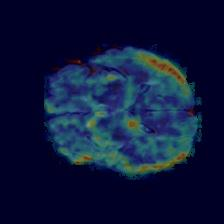

Current unsupervised anomaly localization approaches rely on generative models to learn the distribution of normal images, which is later used to identify potential anomalous regions derived from errors on the reconstructed images. However, a main limitation of nearly all prior literature is the need of employing anomalous images to set a class-specific threshold to locate the anomalies. This limits their usability in realistic scenarios, where only normal data is typically accessible. Despite this major drawback, only a handful of works have addressed this limitation, by integrating supervision on attention maps during training. In this work, we propose a novel formulation that does not require accessing images with abnormalities to define the threshold. Furthermore, and in contrast to very recent work, the proposed constraint is formulated in a more principled manner, leveraging well-known knowledge in constrained optimization. In particular, the equality constraint on the attention maps in prior work is replaced by an inequality constraint, which allows more flexibility. In addition, to address the limitations of penalty-based functions we employ an extension of the popular log-barrier methods to handle the constraint. Comprehensive experiments on the popular BRATS'19 dataset demonstrate that the proposed approach substantially outperforms relevant literature, establishing new state-of-the-art results for unsupervised lesion segmentation.